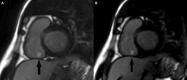

The Society for Cardiovascular Magnetic Resonance (SCMR) is an international society focused on the research, education, and clinical application of cardiovascular magnetic resonance (CMR). Case of the week is a case series hosted on the SCMR website ( https://www.scmr.org ) that demonstrates the utility and importance of CMR in the clinical diagnosis and management of cardiovascular disease. Each case consists of the clinical presentation and a discussion of the condition and the role of CMR in diagnosis and guiding clinical management. The cases are all instructive and helpful in the approach to patient management. We present a digital archive of the 2020 Case of the Week series of 11 cases as a means of further enhancing the education of those interested in CMR and as a means of more readily identifying these cases using a PubMed or similar search engine.